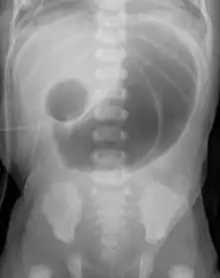

Double bubble (radiology)

Frontal view of the abdomen with double bubble sign, patient was found to have duodenal atresia.

In radiology, the double bubble sign is a feature of pediatric imaging seen on radiographs or prenatal ultrasound in which two air filled bubbles are seen in the abdomen, representing two discontiguous loops of bowel in a proximal, or 'high,' small bowel obstruction. The finding is typically pathologic, and implies either duodenal atresia, duodenal web, annular pancreas, or on occasion midgut volvulus, a distinction that requires close clinical correlation and, in most cases, surgical intervention.[1][2][3]